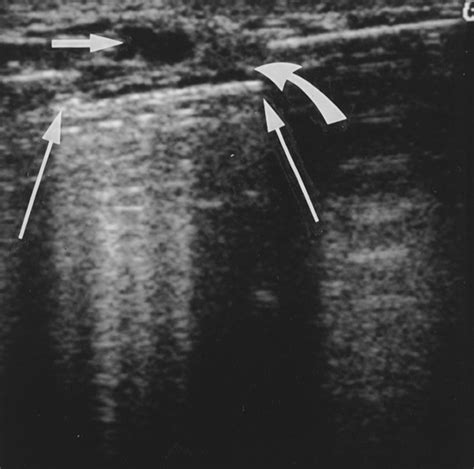

Ultrasound

An ultrasound uses sound waves to create images of the breast tissue. This procedure can help identify cysts, tumors, or other abnormalities that may not be visible on a mammogram.